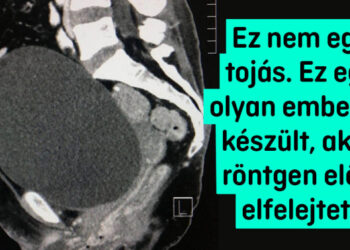

1895-ben Wilhelm Conrad Röntgen felfedezte a röntgensugarakat, külön kiemelve, hogy bár képesek áthatolni az emberi szöveteken, nem tudnak áthatolni például a csontokon vagy a fémeken. Azóta az emberiség mindig a röntgengépekhez nyúl, ha meg akarja vizsgálni egy ember, állat vagy egy hétköznapi tárgy belsejét. A röntgensugarak segítségével egy egészen új, korábban láthatatlan és ismeretlen világ tárult elénk. 1. ,,Röntgenfelvételek egy...